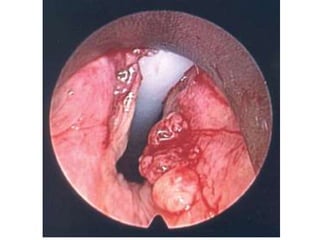

LARYNGITIS

POLYPS

PAPILLOMAS

CARCINOMAS